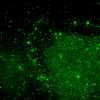

Neuronal Ceroid Lipofuscinosis (NCL) (5)